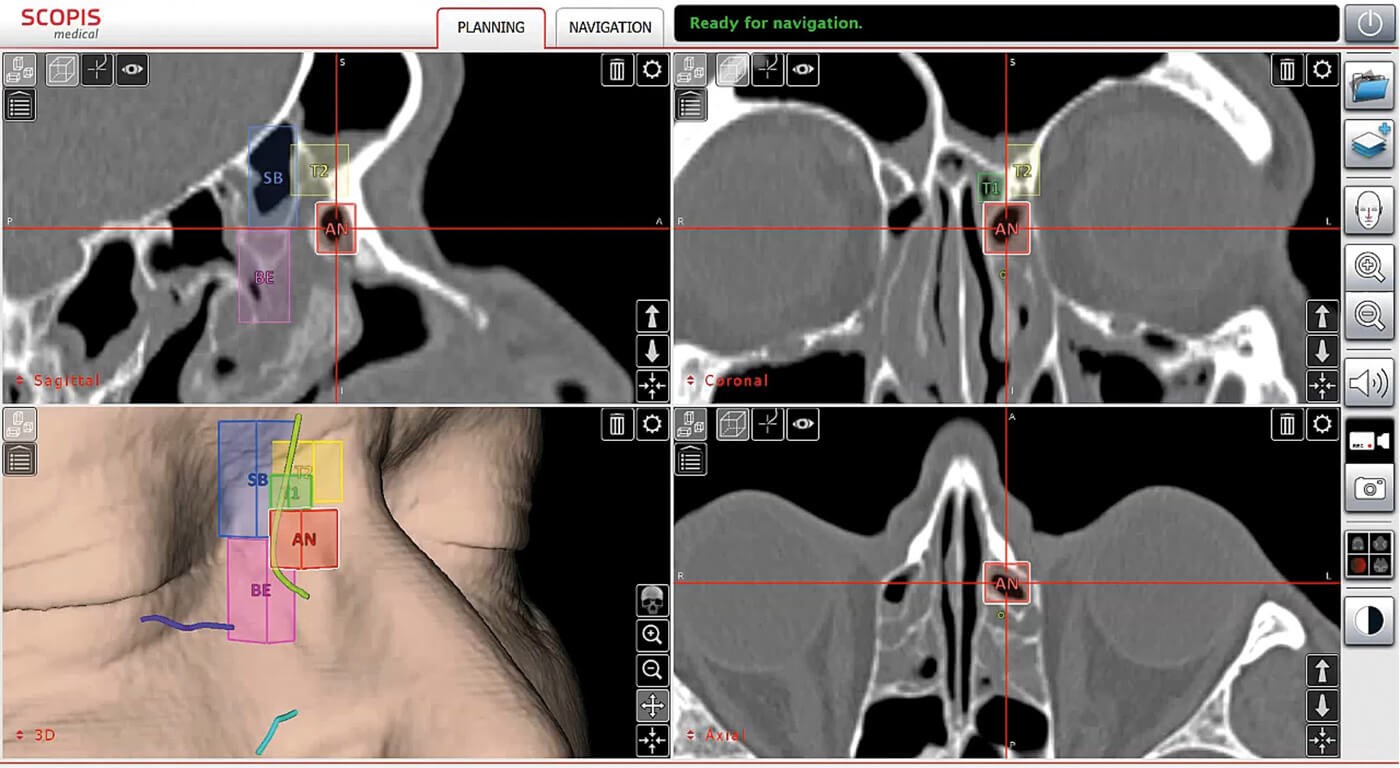

Figure 3: Use of the TGS software to analyse the individual anatomy of pneumatised sections of the paranasal sinuses and for planning paths for surgery (Scopis®). The International Classification of Sinus Anatomy based on Wormald’s Building Block System is used [10]. (© Oliver Kaschke)

A real innovation in IGS has been the implementation of new software functions within navigation systems. Using dedicated graphical elements in the 3D CT or MRI data set, it is now possible to mark anatomical structures and perform formalised preoperative planning (Figure 3). Anatomical classification systems can be used to systematise preoperative analysis and help minimise risk during surgery [6]. Trajectories (surgical access corridors) and danger zones can be defined during planning and then visualised intraoperatively on the monitor within the endoscopic image. This ‘augmented reality (AR)’ capability was realised, for example, with the navigation system developed by Scopis (Germany; Figure 4).